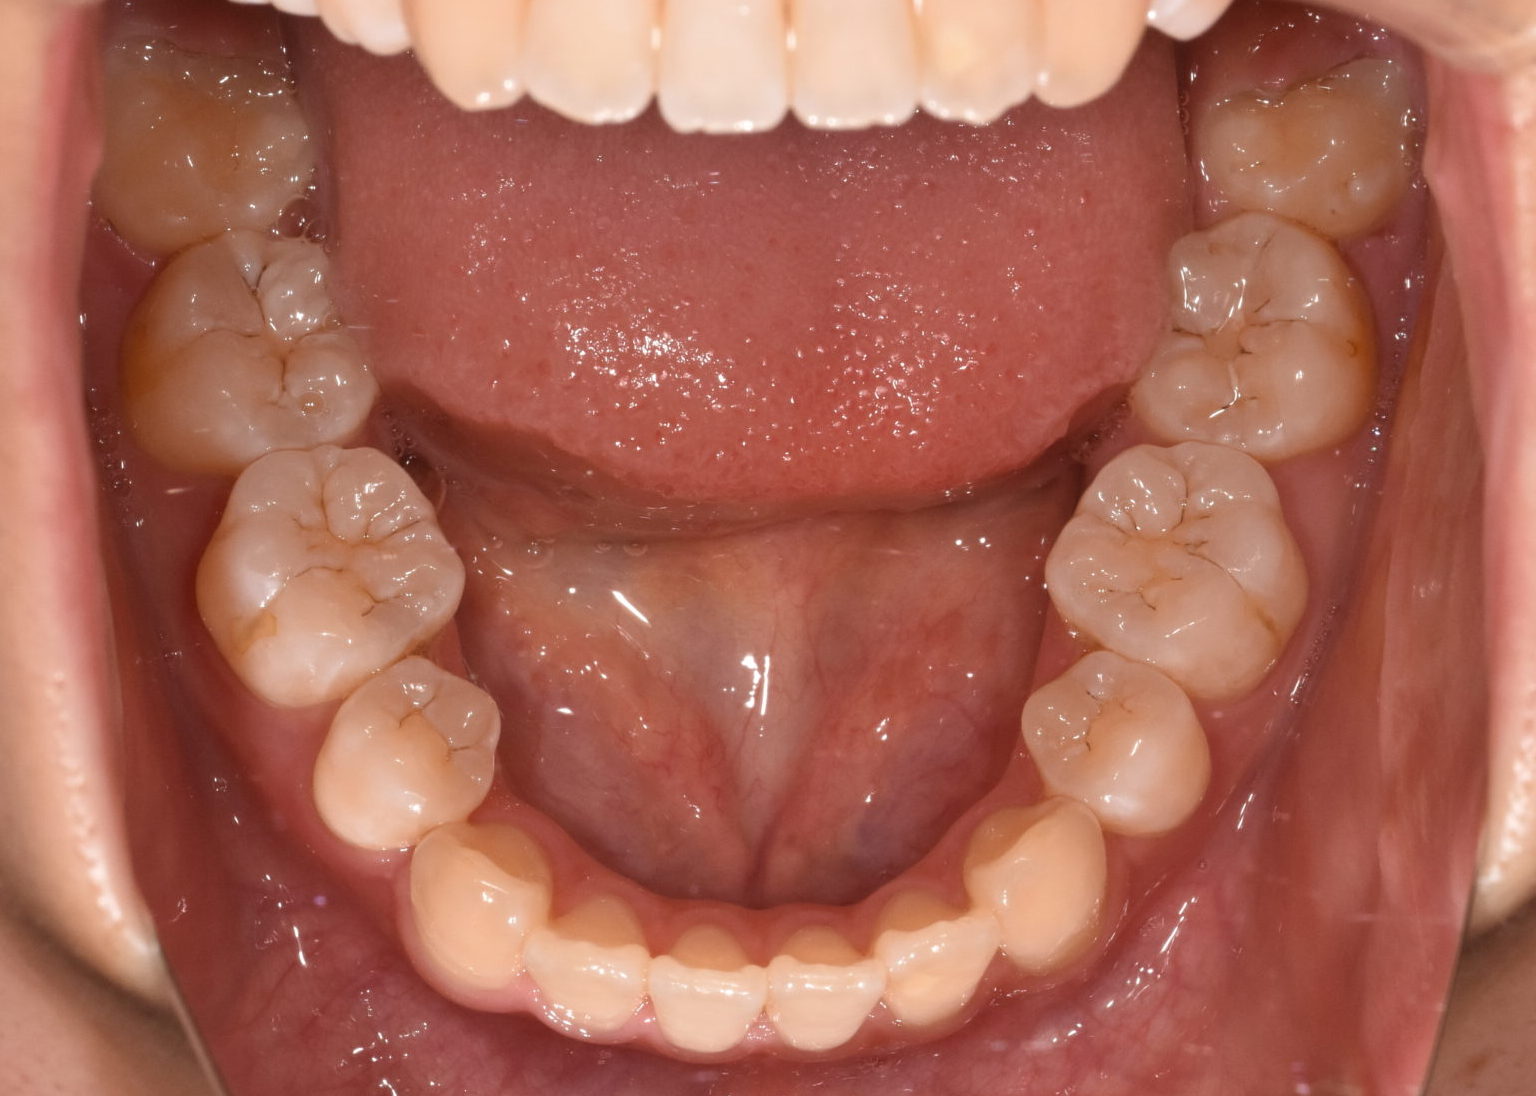

治療前

お悩み:

前歯が噛み合わず、食べ物が噛みにくい

状態:

骨格:開咬傾向(前歯が噛みにくいタイプ)

歯並び:前歯が噛み合わない(開咬)+前歯の突出傾向

治療方法:

上下左右の第1小臼歯(4番)を抜歯し、マウスピース型矯正装置を用いて歯並びとかみ合わせの改善を行いました

治療のポイント:

・抜歯によりスペースを確保し、前歯の位置と角度をコントロール

・マウスピース矯正により、見た目と快適さに配慮しながら治療

・奥歯の高さを調整し、前歯がしっかり噛むように改善

・舌のクセ(舌突出癖)にも配慮し、後戻りを予防